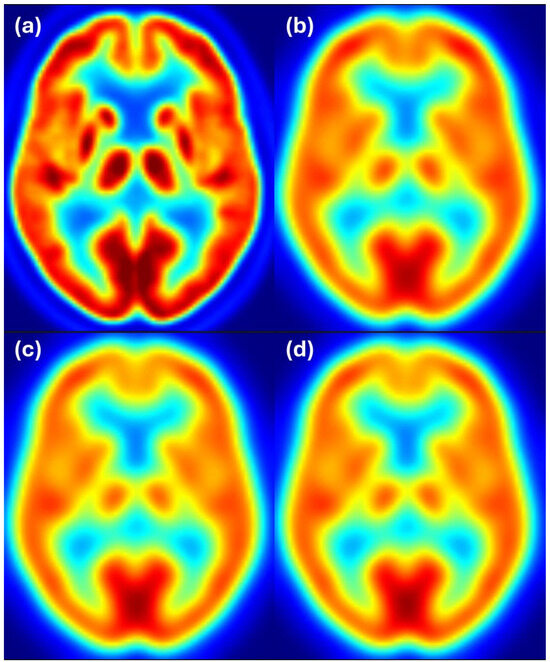

Figure 6 shows axial slices for 6 mm target resolution for HR+ matching HRRT resolution—the combination where the estimated filter considerably differs from the ground truth. We see that the HR+ image after filtering with the estimated filter follows the reference image at 6 mm resolution, while the HR+ and HRRT images at 6 mm resolution appear to have slightly different resolution. Color scale indicates FDG uptake levels: red for high, green/yellow for medium, and blue for low uptake.

Figure 6. Harmonization results for the HR+ scanner matching the HRRT images filtered to 6 mm resolution. Image (a) shows the unfiltered HR+ image, (b) shows the HRRT image at the target resolution of 6 mm, (c) shows the HR+ image after filtering with the estimated filter, and (d) shows the HR+ image filtered to 6 mm resolution. Color scale indicates FDG uptake levels: red for high, green/yellow for medium, and blue for low uptake.